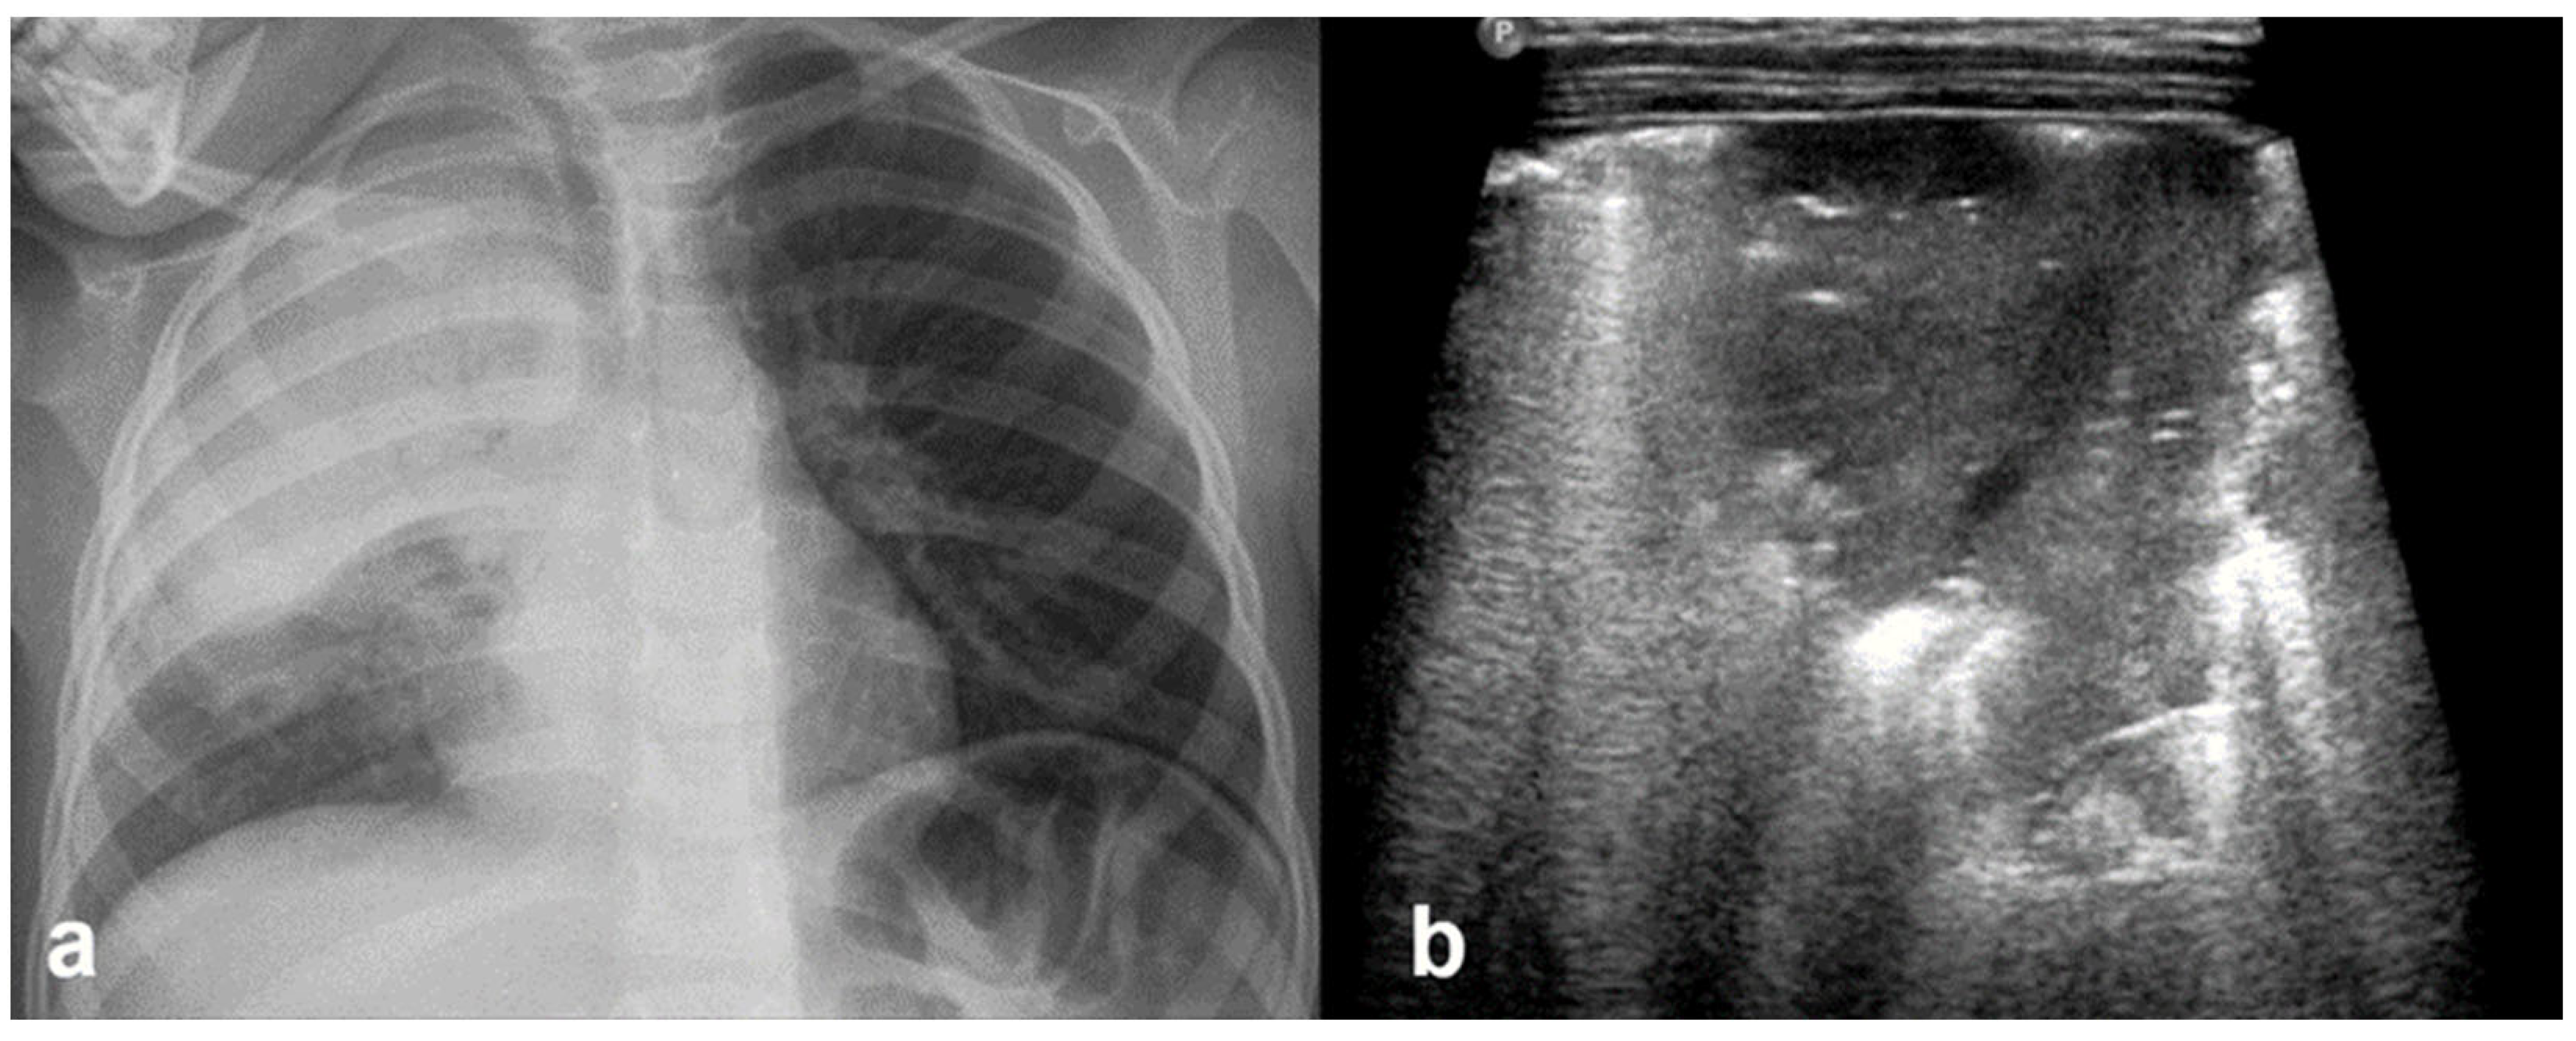

3.2.10. Pleural Effusion

Pleural effusion, defined as the accumulation of fluid in the pleural space, can be easily detected by LUS, which is highly sensitive and able to identify even small volumes of fluid (as little as 5–20 mL). In contrast, effusions greater than 175–250 mL must typically be present for the detection of pleural effusion by conventional chest X-rays, although lateral decubitus views may detect effusions of approximately 50 mL. A pure pleural effusion typically appears as an anechoic collection located between the parietal and visceral pleura, often seen as a clear, dark space (fluid) that allows for the visualization of underlying lung structures and diaphragm movement [13,20,35,54].

In contrast, complicated effusions may exhibit internal echogenicity due to the presence of fibrin, debris, or infection. Identifying the nature of the effusion, in other words whether it is simple effusion or complicated, is critical for clinical decision-making, and may help indicate the need for drainage, antibiotic therapy, or surgical intervention. Thus, LUS can be considered to play a pivotal role in both the diagnosis and management of pleural effusions, particularly in neonates and critically ill patients [10,23].